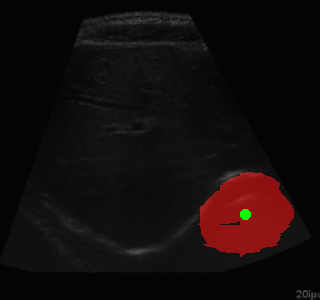

Segmentation Example Segmentation Example Segmentation Example

Example of segmentation results on an abdominal ultrasound image. The top left in the above is the orginal cropped image of the Ultrasound , the top right shows the mask_cropped image after the segmentation . Then combining these two we get our overalled_cropped image where the red overlay shows the segmented region of interest.